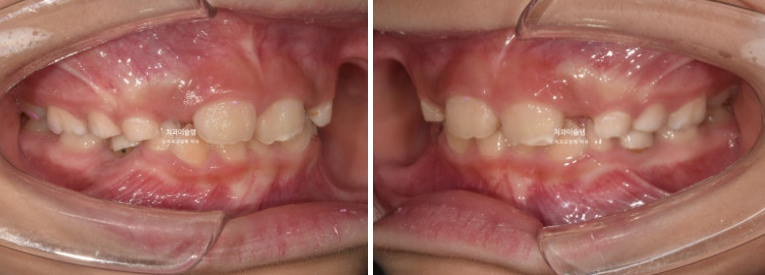

23.10~25.08